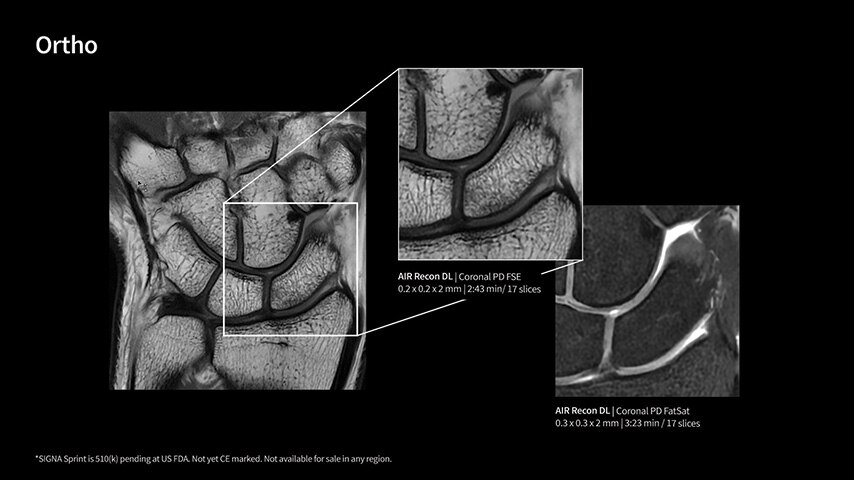

With GE HealthCare's comprehensive suite of deep-learning solutions integrated into SIGNA Sprint, you can unlock the full potential of your MRI system. No need for complicated patient setups or imaging protocols. The exceptional intelligence of our AI solutions offer multiple benefits, with AIR Recon DL giving pin-sharp images, Sonic DL accelerating scans up to 12x, and AIR x enabling automated slice placement. All helping to enhance your department’s workflow efficiency, increase patient throughput, and get the diagnostic clarity you need, faster.¹ Meaning you can spend more time on what truly matters—personalized patient care, enabling optimized treatment plans and treatment response monitoring—ultimately, supporting better clinical outcomes.